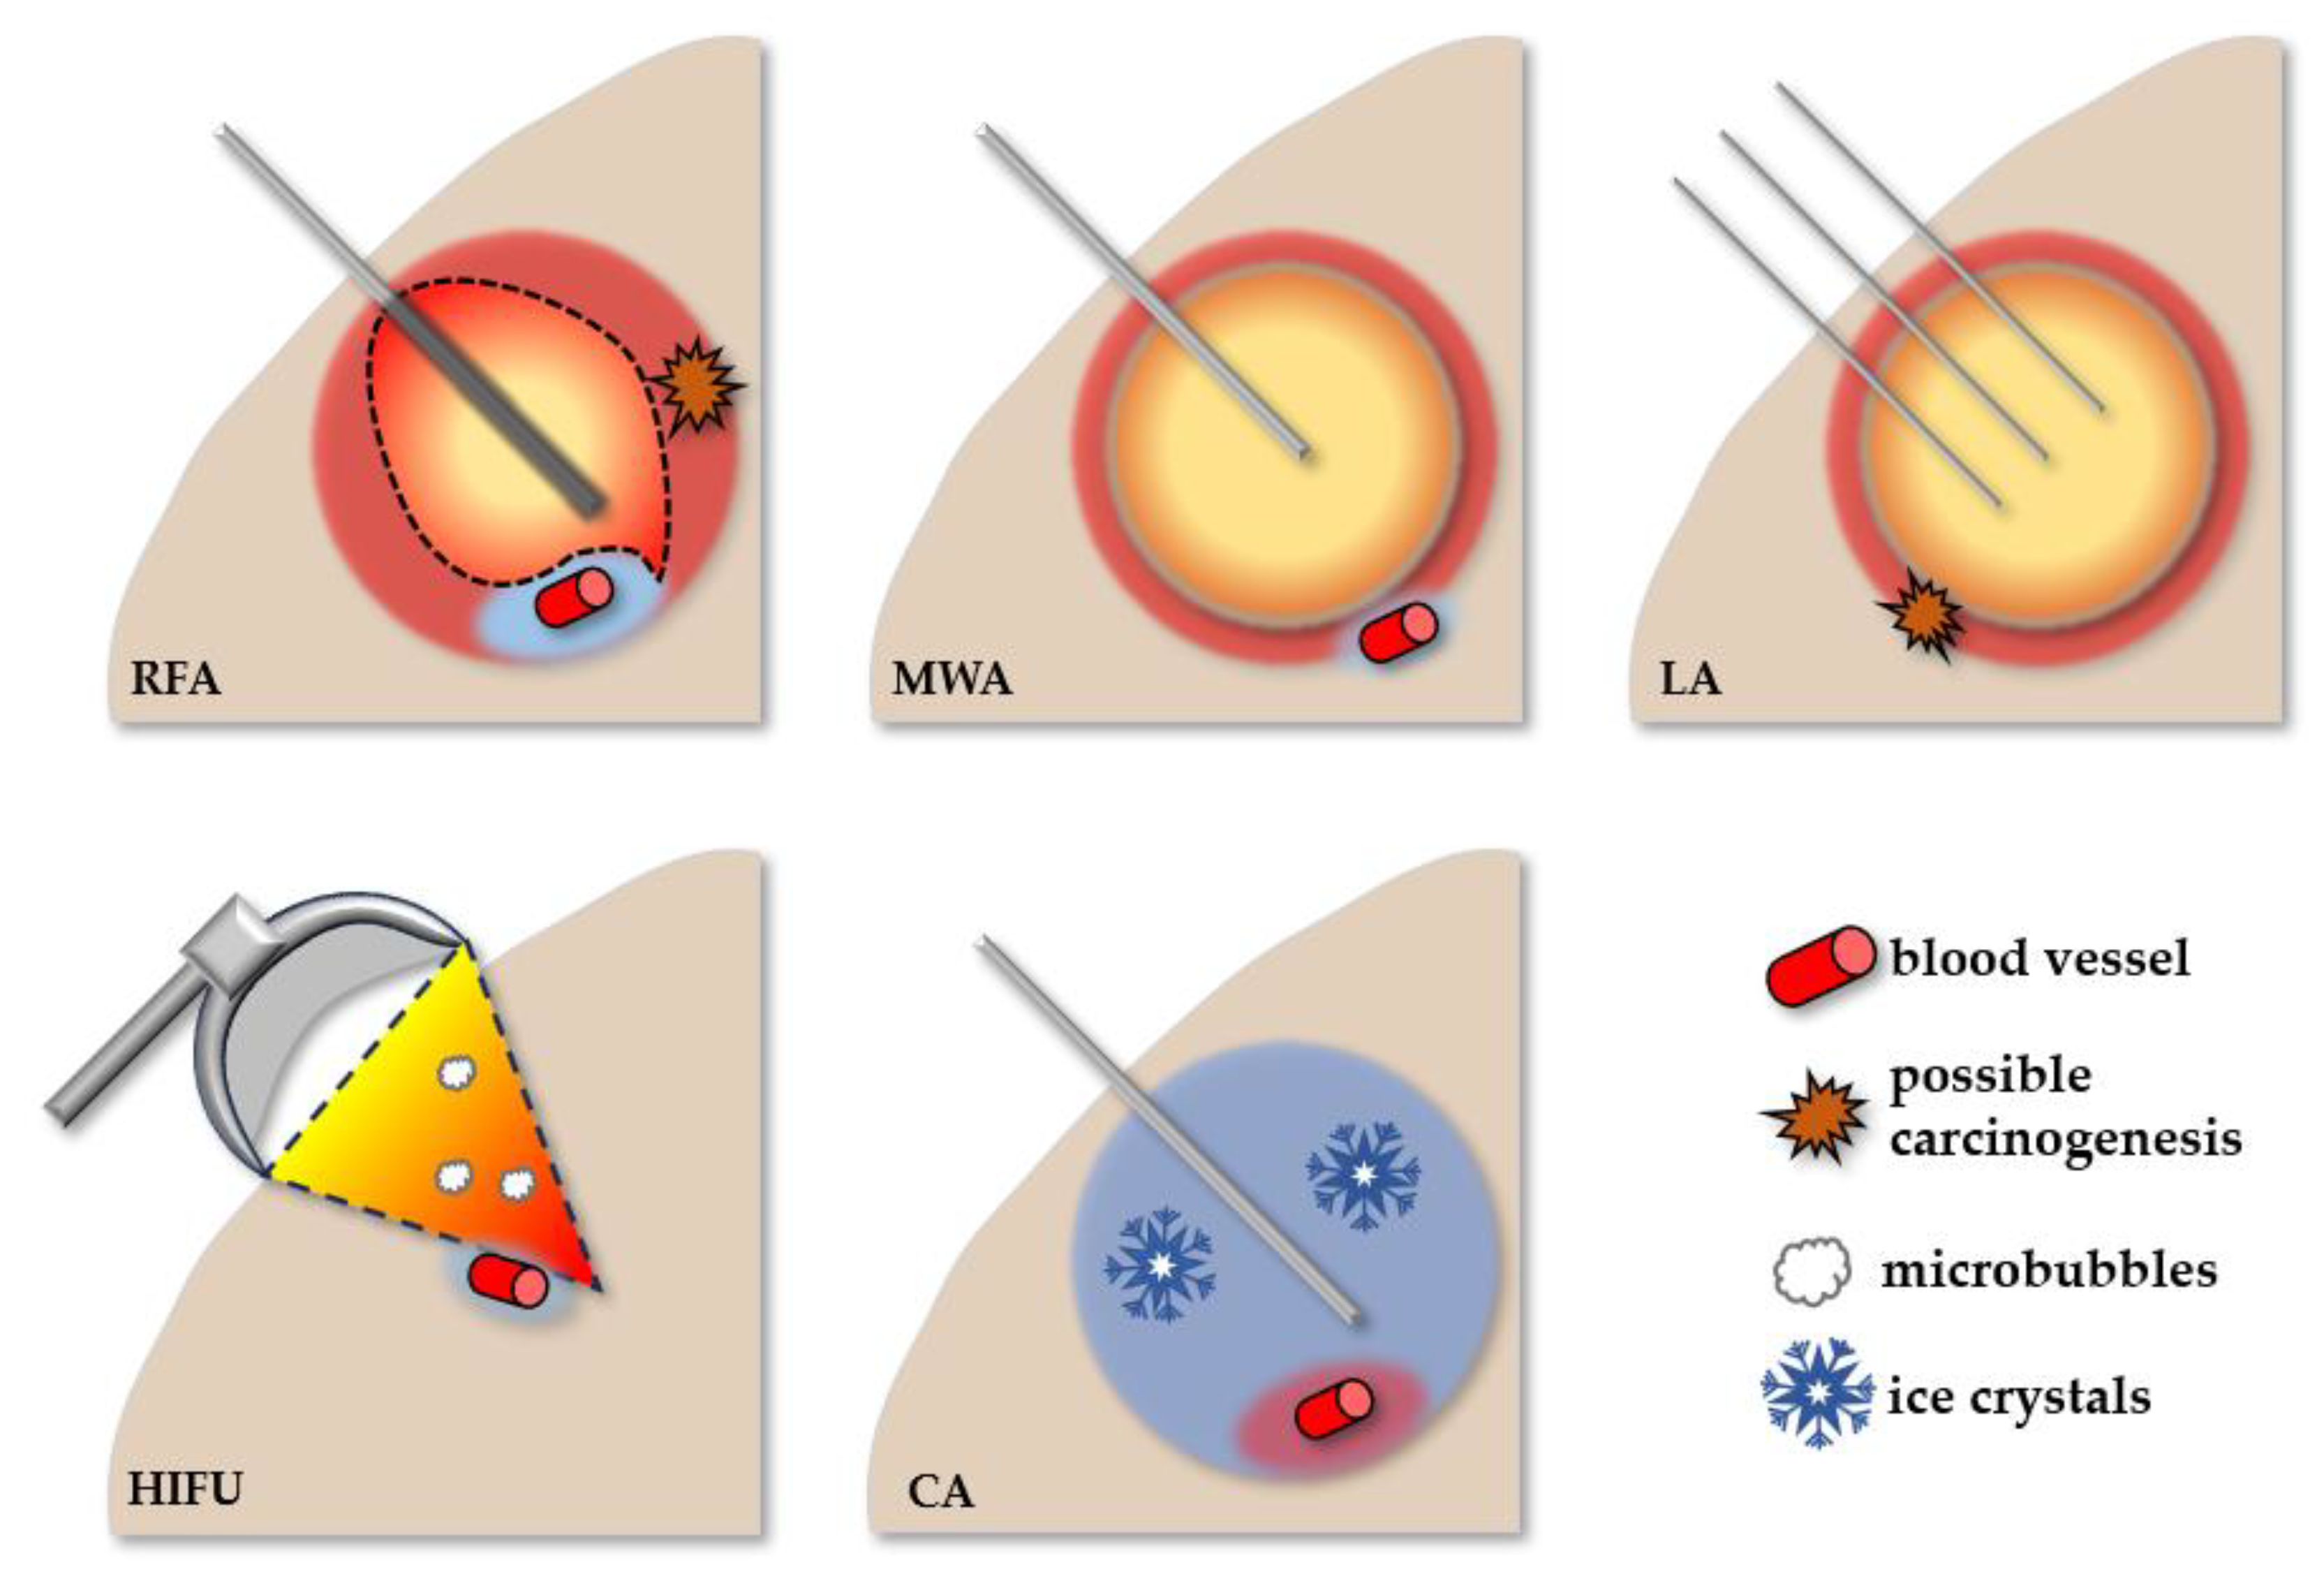

2. Minimally Invasive Therapies for HCC and Their Tissular Effects

2.1. Thermal Ablative Therapies

2.1.1. Radiofrequency Ablation

2.1.2. Microwave Ablation

2.1.3. Laser Ablation

2.1.4. High-Intensity Focused Ultrasound

2.1.5. Cryoablation